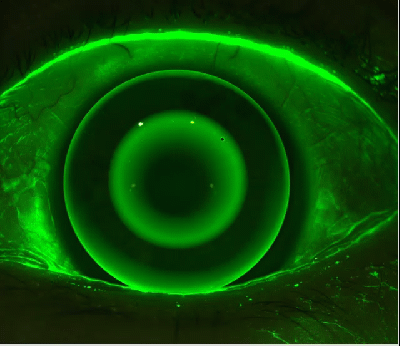

The medmont meridia was designed to give your practice a standardized choice with many clinical applications in a single platform. Along with the advancement in corneal topography technology, medmont meridia also expands your choices and business. Choices, such as, premium Anterior and Fluorescein imaging and videos, enhanced Meibography imaging, clear Tear Meniscus Height and Tear Break-up Time measurements and more. Overall, the new standard in Medmont topography enables higher per-patient and space utilization while allowing you to develop and extend your dry eye and specialty lens business — optimizing your ROI.

Fluorescein Image and Video |

✓ |